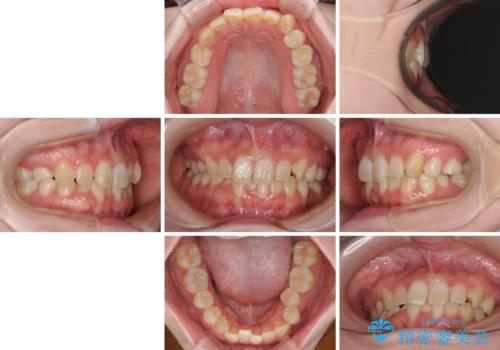

ディープバイトをインビザライン矯正で改善

- 前歯のデコボコと強い咬みしめを気にして来院された患者様です。

インビザラインを用いて、前歯の叢生を解消するとともに、ディープバイトを改善していくこととしました。